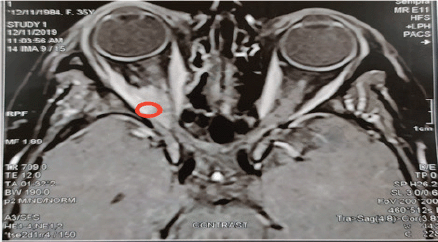

We report a case of a 31-year-old patient who was diagnosed with T2N2M0 Estrogen Receptor(ER)/Progesterone (PgR) positive/HER-2/neu negative, Ki-67 > 30% right breast cancer. She was treated with modified radical mastectomy followed by adjuvant chemotherapy with six cycles of FAC regimen (5-Fluorouracil (5-FU) 600 mg/m2 IV, Doxorubicin 60 mg/m2 IV, Cyclophosphamide 600 mg/m2 IV) every 21 days, radiotherapy (RTH) and adjuvant hormonal treatment with Tamoxifen for 2 years. The patient presented with severe back pain and the bone scan showed multiple bone metastases while multi-slice computed tomography (MSCT) of the chest and pelvis-abdomen were insignificant so she was shifted to luteinizing hormone-releasing hormone (LHRH) analogues in combination with Fulvestrant and palliative RTH. Eleven months later, the patient experienced successive bone progression and thereafter was shifted to aromatase inhibitors. Six months later, on November 2019 (4 years after the initial diagnosis), the patient presented with right eye ptosis, and the magnetic resonance imaging (MRI) of the brain and orbit showed a soft tissue mass in the superior and lateral rectus muscles (Figure 1) with no evidence of visceral metastasis on further metastatic work up except for multiple bone lesions.

Figure 1. MRI brain at dignosis: T1 with contrast shows right superior rectal muscle thickening about 14 mm associated with slight proptosis of the right eye.